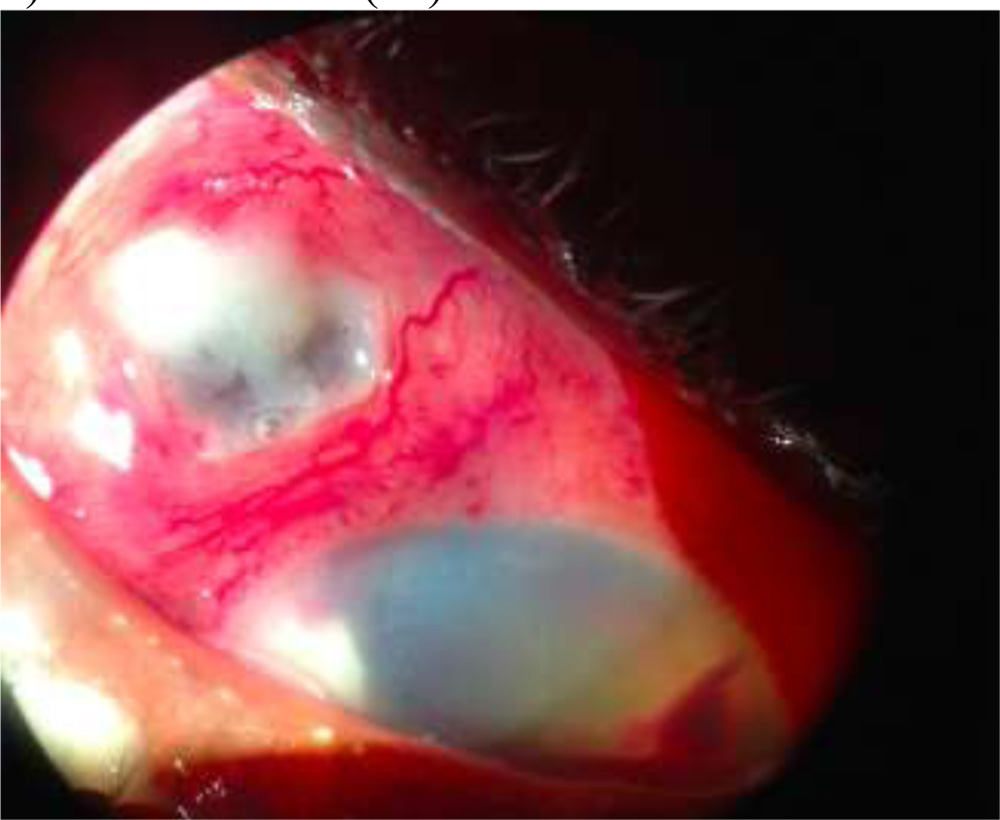

4) Scleral Abscess(26)

Fig:7:- Scleral Abscess in NocardialEndophthalmitis